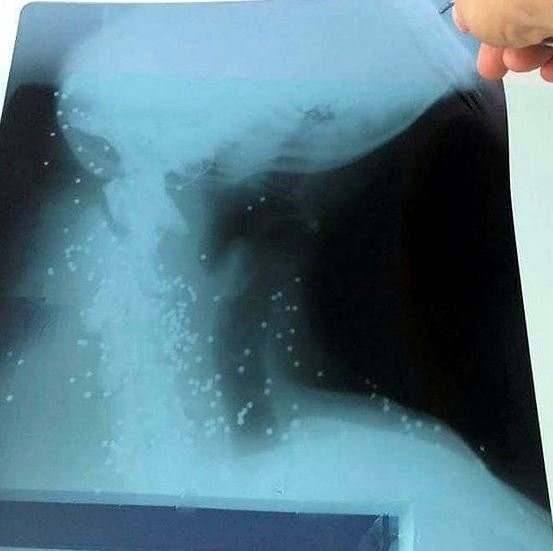

Bitez sahilinde yaralı bir halde yatan köpeği gören vatandaşlar durumu hayvan hakları derneği başkanı Füsun Uslu'ya bildirdi. Köpeği acil olarak veterinere götüren Uslu, gördüğü manzara karşısında şoke oldu. Yaralı köpeğe müdahale eden veteriner, hayvanın neden bu halde olduğunu araştırmak için röntgenini çekti. Röntgeni inceleyen veteriner köpeğin vücudunda soluk borusuna kadar saçma olduğunu gördü. Yaralarına pansuman yapılan ve saçmaları temizlenen köpek daha sonra Bodrum Belediyesi Hayvan Barınağına götürüldü. Köpeğin tedavisinin devam ettiği ve durumunun ciddi olduğu öğrenildi.

Bodrum Hayvan Hakları Derneği Başkanı Füsun Uslu konuyla ilgili Bitez sahilinde araştırma yaptıklarını belirterek, "Bizi bir vatandaş aradı sahilde yaralı bir köpek var diye. Bitez sahilinde yaralı bir köpek olduğunu söyledi. Biz hemen köpeği alıp veterinere götürdük. Orada röntgenleri çekildi. Hayvanın durumu iyi değil, soluk borusuna kadar saçma var. Konunun peşindeyiz" dedi.